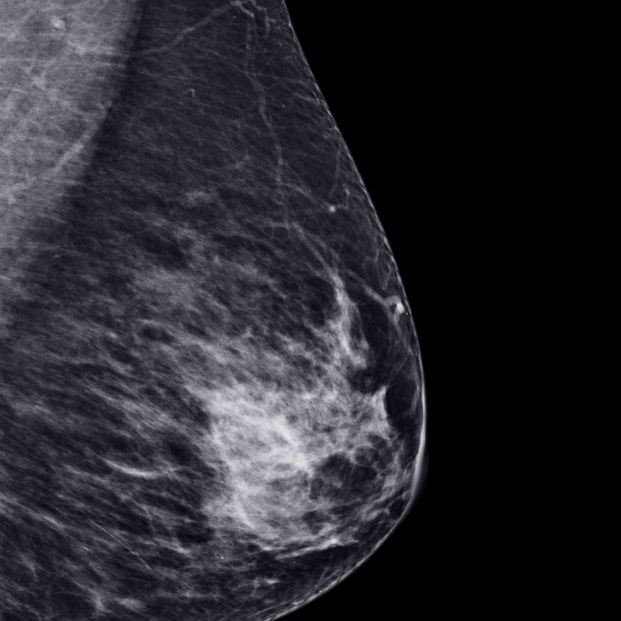

A día de hoy en España y Europa existen tres cribados recomendados: el de cáncer de mama mediante mamografía cada dos años en mujeres con edades entre 50 y 69 años; el de cáncer de colon y recto mediante la detección de sangre oculta en heces en personas entre 50 y 69 años, y el de cuello uterino mediante detección del virus del papiloma humano (VPH) en combinación con la vacunación del mismo.